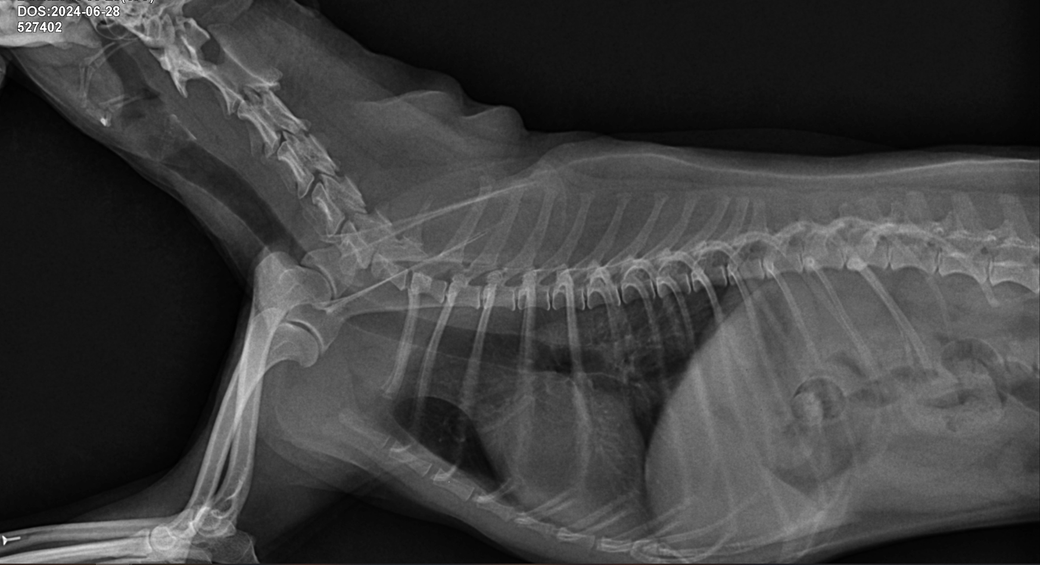

기관지협착인가요 기관협착인가요? 아니면 둘다 있나요? 기관지염이 있나요? 기관염이 있나요?

질문1. 기관지협착인가요 기관협착인가요? 아니면 둘다 있나요?

질문2. 기관지염이 있나요? 기관염이 있나요?

질문3. 사진 좌측상단에 날짜부분에 굉장히 좁아보이는데 이부분이 후두인가요? 후두가 부어있는건가요?

질문4. 약간의 기도협착이 있나요?

질문5. 협착과 염 상태가 어느정도인지 상중하로 알려주시면 감사하겠습니다

1. 기관 혹은 기관지 협착은 동적 질환으로 이 사진 한장으로 진단할 수 없습니다.

2. 있다고 이야기 할 수 없지만 동시에 없다고 말할 수 없는 자료입니다.

3. 후두이고 부어 있는것은 방사선으로 평가하는게 아니라 육안 평가를 해야 합니다.

4. 평가할 수 없는 사진입니다.

5. 평가할 수 없는 사진이기 때문에 알려드릴 정보가 없습니다.

주치의와 협의하에 기관협착, 기관지염 등을 진단하는 다른 진단검사들을 진행하시기 바랍니다.